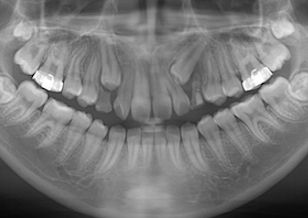

Before Ⅳ

上顎骨の劣成長に起因する骨格性反対咬合(上下顎骨の前後的な位置不正が原因)で、前歯部は反対咬合となっており咀嚼障害を認めます。 上下顎歯列において叢生(ガタガタの歯並び)と 上下顎歯列の正中線のズレが認められます。 左側上下顎第一大臼歯は交叉咬合となっています。レントゲン所見では、上顎左側犬歯が方向異常にてその隣の側切歯の歯根にぶつかって埋伏していました。

Before Ⅳの写真は、治療中のパノラマレントゲンです。(上顎左側犬歯が方向異常にてその隣の側切歯の歯根にぶつかって埋伏しています。)